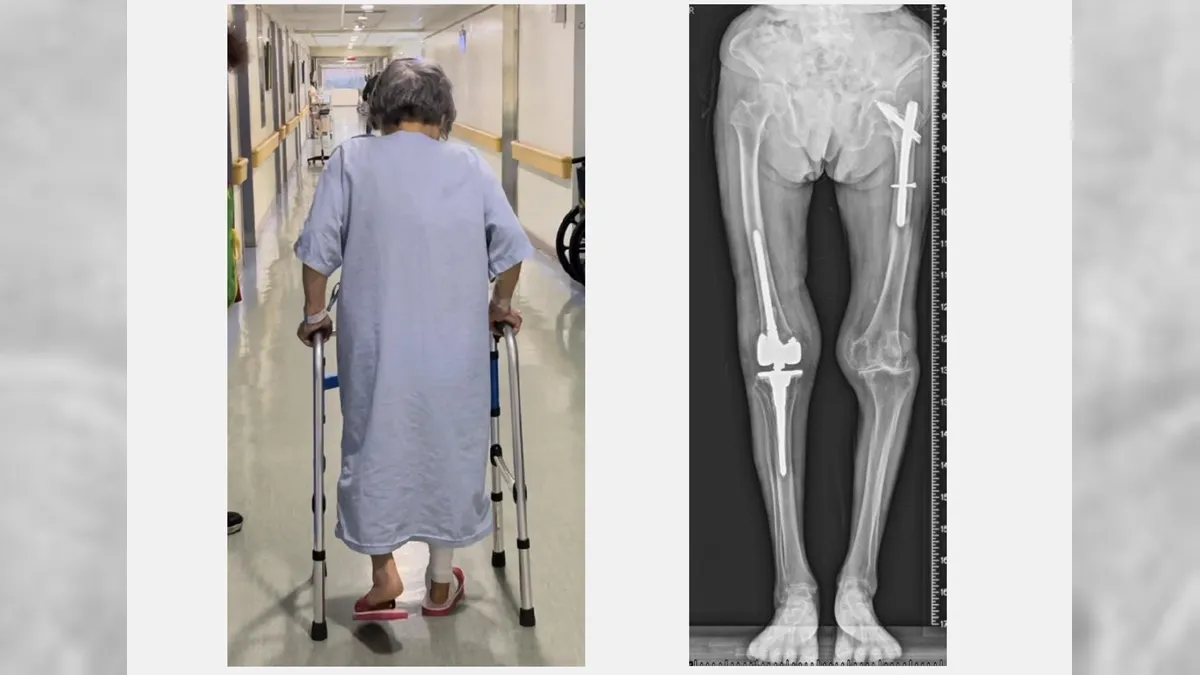

黃贊文說,當初黃奶奶由家屬推著輪椅來到門診時一臉沮喪。X光檢查顯示她的人工膝關節旁出現粉碎性骨折,由於年紀大骨質疏鬆嚴重,人工關節就像地基出現天坑一樣整個鬆動。

由於黃奶奶骨質疏鬆嚴重,不僅出現粉碎性骨折,也連帶傷及膝關節韌帶。黃贊文使用新式預鎖式樞紐設計的人工關節,能取代韌帶功能並填充骨頭缺損,重建穩定的膝關節。令人非常敬佩的是,老太太堅持「站起來走路」的決心,她手術當天下午就能自己拿著助行器下床上廁所。

從手術隔天開始,除了骨質疏鬆症的治療,團隊還為老太太安排手術後疼痛中醫輔助醫療。復健科醫師根據她的需求安排復健運動,在病床邊開始固定式腳踏車訓練。在手術後第5天,黃奶奶便能開心地走路出院回家。